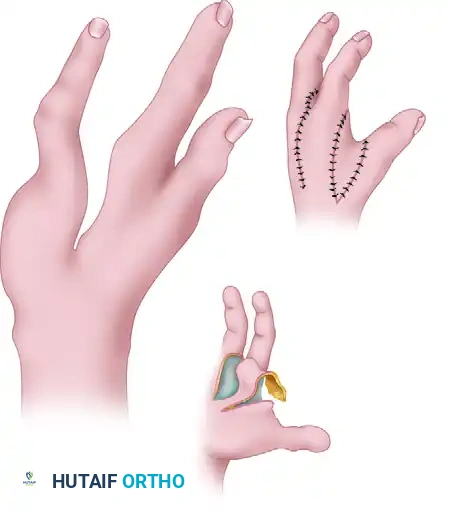

4. Wound Closure and Web Space Inset

- Suture the skin between the ring and index fingers, closing the central cleft.

- Inset the small, longitudinal flap into the ulnar side of the index finger to recreate a smooth, U-shaped commissure.

- Transpose the large palmar-based cleft flap into the newly opened space between the index finger and the abducted thumb.

Relationship of the thumb adduction contracture release and the palmar flap. If the palmar flap is insufficient to cover the defect, a full-thickness or split-thickness skin graft must be utilized.

- Tension-Free Closure: Never place these flaps under tension. Ischemia will lead to flap necrosis and severe secondary contracture. If the palmar flap does not completely cover the dorsal defect, harvest a split-thickness or full-thickness skin graft to achieve complete, tension-free coverage.

- Insert a small surgical drain if dead space or oozing is a concern.